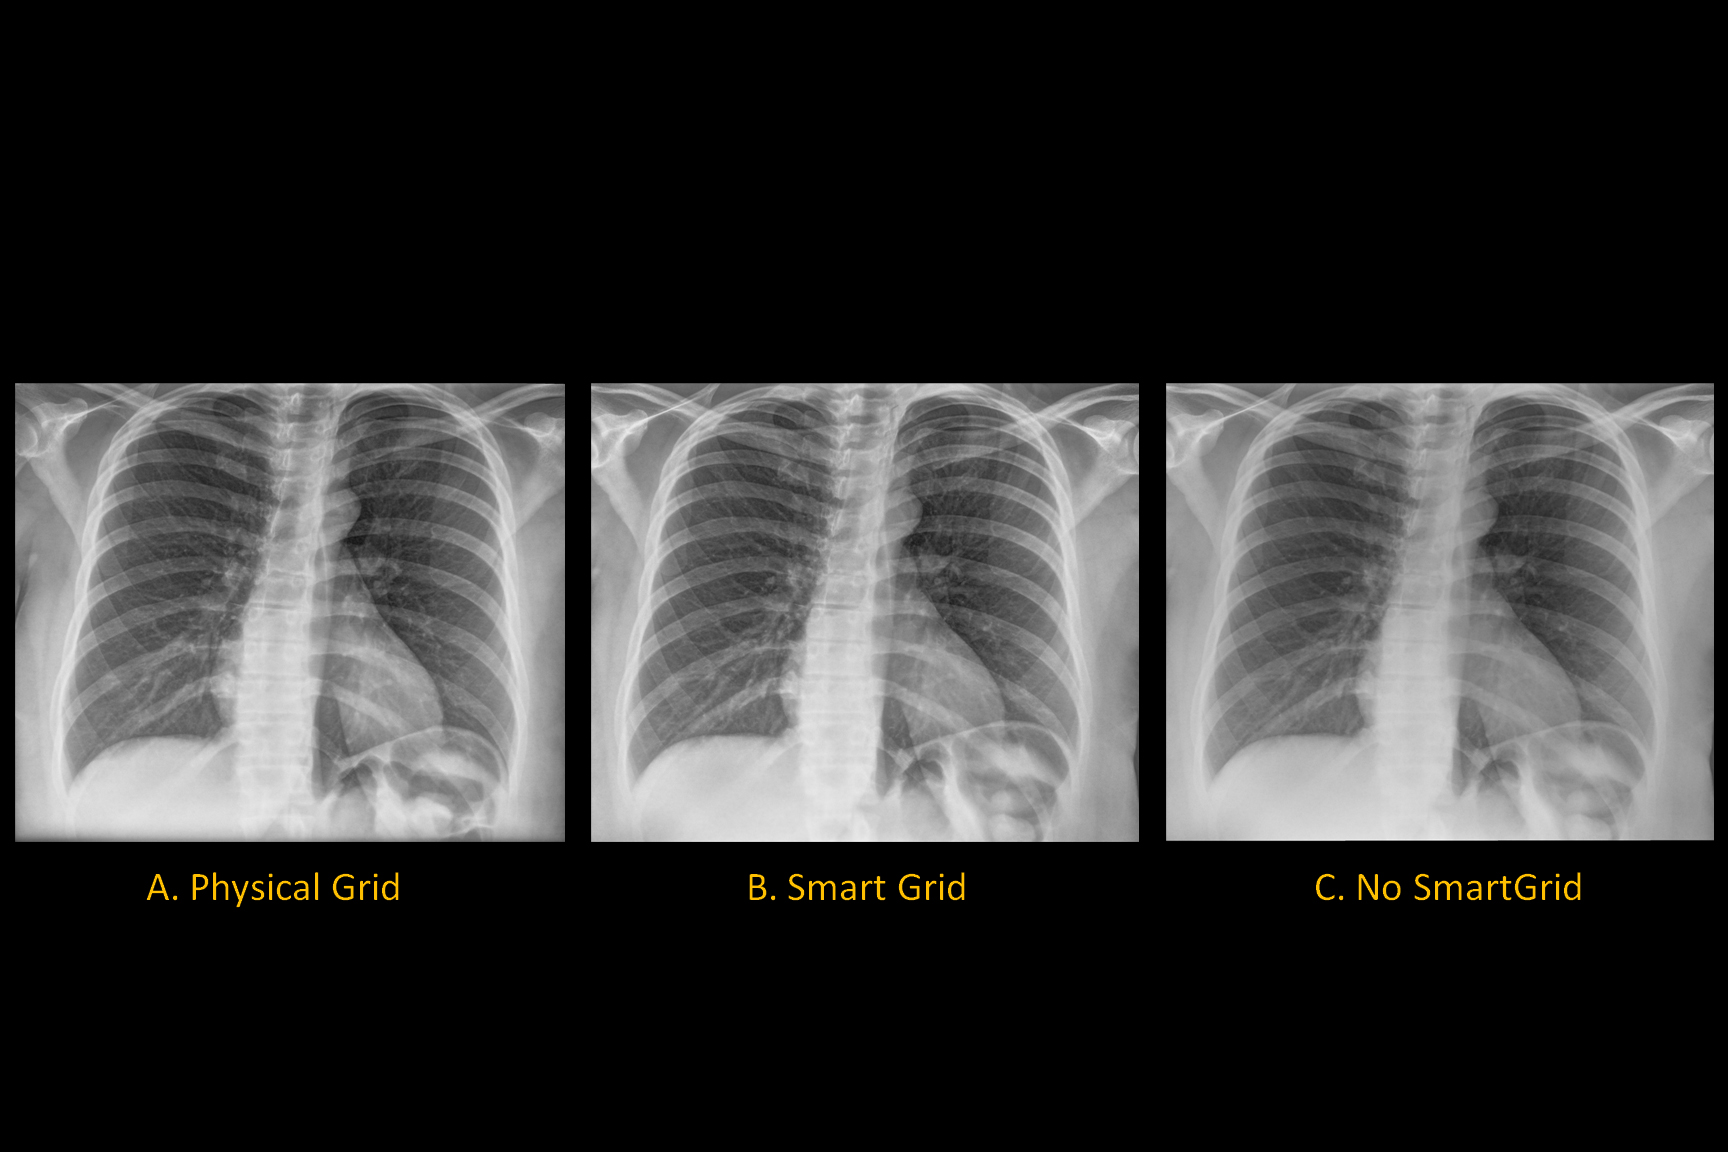

Noise in virtually all x-ray imaging modalities is dominated by quantum mottle where the latter relates to the total number of x-rays used to generate an image. A typical x-ray beam used in abdominal radiography would likely have an HVL of 3 mm of aluminum. This means that exposing the detector in the absence of an object would result in a grainy image rather than uniform greyscale.